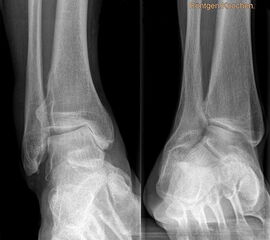

Auf dem linken Bild (a) Varusarthrose des oberen Sprunggelenks mit deutlicher Mehrbelastung der medialen Gelenkanteile. Dort bereits deutlich sichtbarer Knorpelverlust. Rechtes Bild (b) Valgusarthrose des oberen Sprunggelenks. Erhöhte Druckbelastung in de

Es wurde in der gleichen Arbeit auch das Alignement der arthrotischen Sprunggelenke untersucht. Insgesamt lag nur in 37% der Fälle ein physiologisches Alignement vor, 55% der Gelenke waren varisch eingestellt, 8% valgisch.